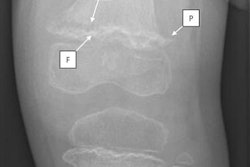

(A) Negative Vulcan salute sign in a 50-year-old woman from the control group. (B) Positive Vulcan salute sign (V-sign) of the 3/4 interspace in a 46-year-old woman with Morton's neuroma. (C) "Vulcan salute" from one of the authors. Image courtesy of Skeletal Radiology.For those unfamiliar with the "Star Trek" television series and the Mr. Spock character, the Vulcan salute (shortened to "V-sign" in the article) is a hand gesture made by parting the middle and ring fingers while the palm is facing forward and the thumb is extended.

In this retrospective case-control study, Galley and colleagues enrolled 100 patients with MRI-proven Morton's neuroma 2/3 or 3/4 (between the second and third or third and fourth toes) and 100 patients without the condition. Conventional weight-bearing dorsoplantar view radiographs were evaluated for the subjective presence of the V-sign by two blinded, independent musculoskeletal radiologists.

The researchers found a significant difference between the groups regarding the presence of the V-sign, which was found in 30 of 100 patients in the Morton's neuroma group and in three of 100 control patients, with a sensitivity of 30% and a specificity of 97%.